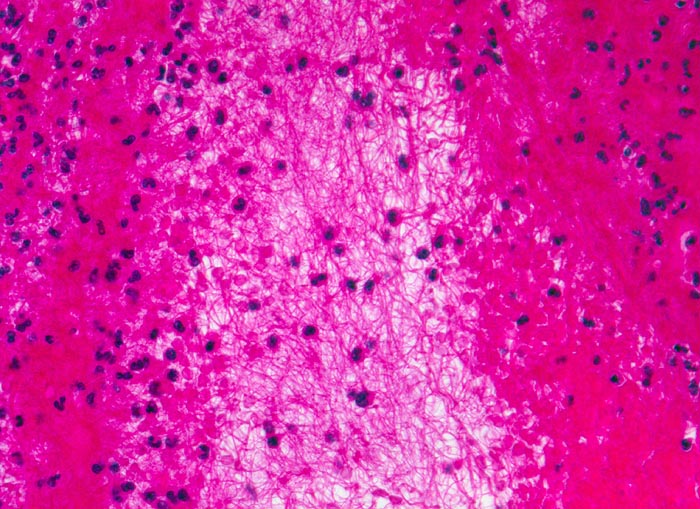

Korallenstockthrombus (Abscheidungsthrombus)

Abscheidungsthrombus bestehend aus abwechselnden Schichten von zerfallenen Thrombozyten mit Fibrin und fädigem Fibrin, in dem sich neutrophile Granulozyten und Erythrozyten verfangen haben.

Makroskopisch sind die verschiedenen Schichten als sogenannte Zahn'sche Linien identifizierbar: hellere Schichten von Fibrin mit Thrombozyten und dunklere Schichten mit Fibrin, Erythrozyten und Granulozyten.